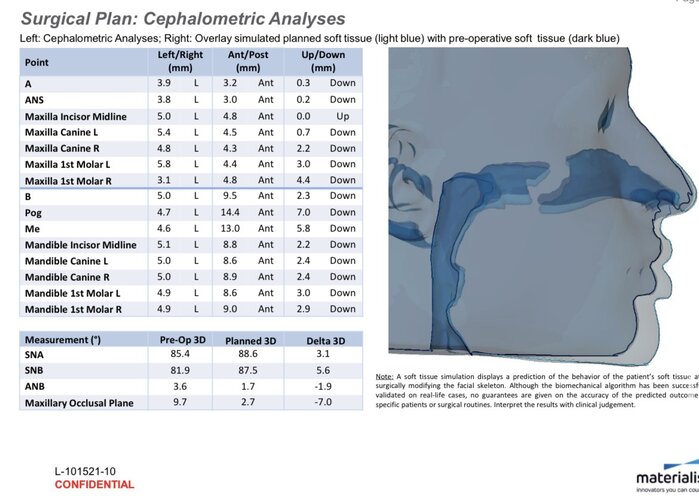

im getting surgery(trimax and infras) soon, any thoughts on this?my left side (the 31 mm) is also less wide in real life, i think would be good to extend it more to the nose area.